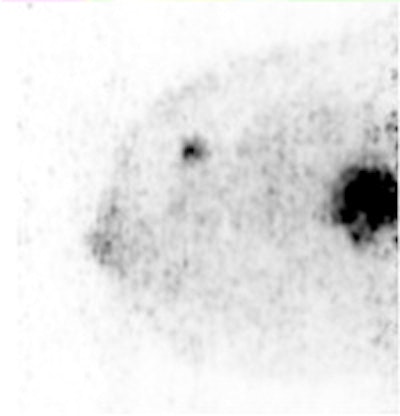

Sagittal Mammi-PET image shows two FDG-avid lesions. The smallest distal lesion, with a diameter of 2 mm, had been classified as benign (BI-RADS 2) on MRI. All images courtesy of Dr. Suzana Teixeira.Patents received 180 MBq to 240 MBq of FDG before undergoing the PEM scan and received a follow-up standard whole-body PET/CT exam.